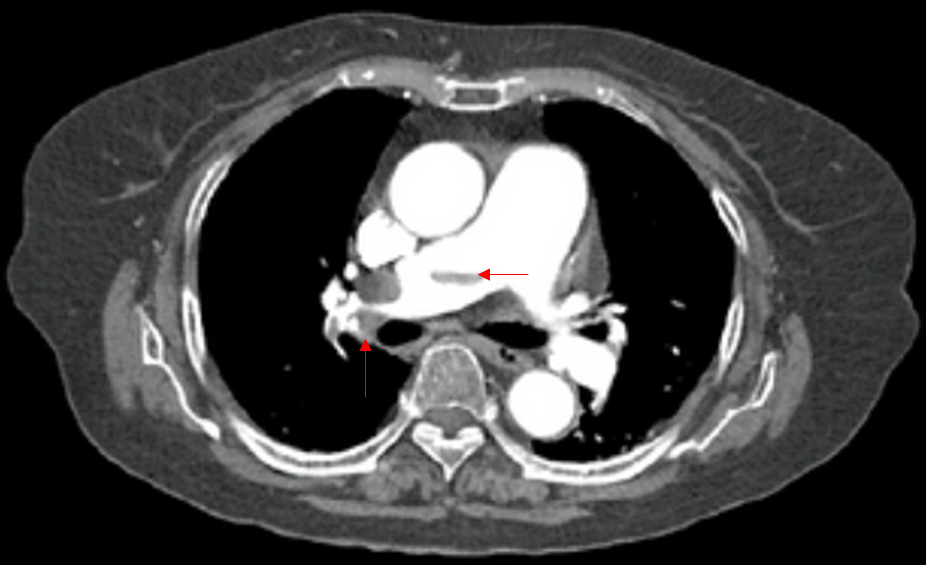

67세 여자가 1시간 전부터 숨이 차서 병원에 왔다. 4개월 전 양쪽 무릎관절대치술을 받은 후 주로 누워 지냈다고 한다. 혈압 78/54 mmHg, 맥박 122회/분, 호흡 24회/분, 체온 36.4℃이다. 목정맥이 늘어나 있고, 오른쪽 다리가 부어 있고 정강뼈 앞 오목부종은 없다. 가슴 컴퓨터단층 촬영 사진이다. 치료는?

Img | Chest CT: 폐동맥 혈전 |

급성 호흡곤란, 장기간 bed rest의 과거력, CT상 혈전이 있으므로 PTE 진단 하, V/S unstable하고 항혈전치료 금기증이 없으므로 t-PA 등의 혈전용해치료를 시행한다.

• CT에서 폐동맥 혈전이 보이므로 폐색전증으로 진단할 수 있다.